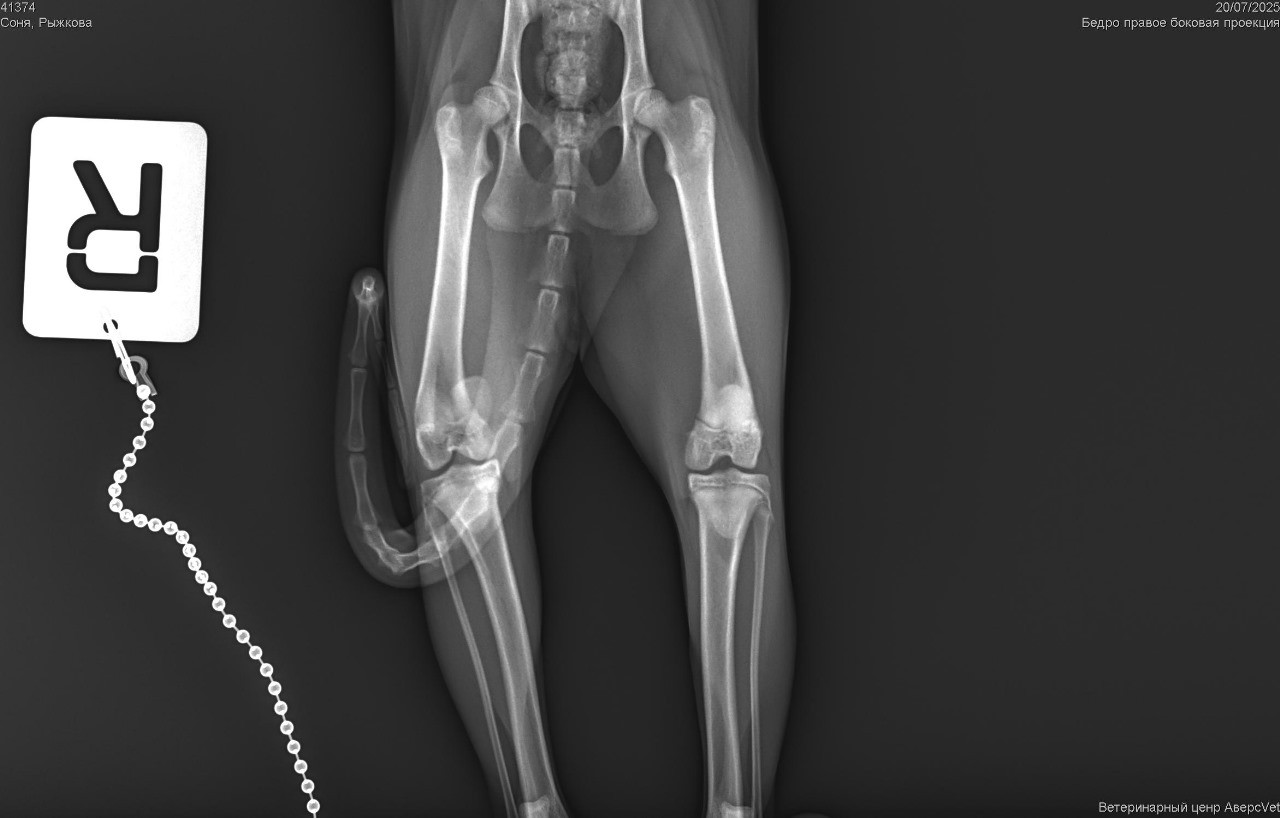

Кошечка сфинкс 6 месяцев,повредила лапку, после рентгена поставили диагноз медиальный вывих коленной чашечки. При ходьбе хромает на заднюю лапку, но вроде как боли не испытывает когда осматриваешь,в ветеринарной клинике сказали что операцию можно и не делать, только всю жизнь будет хромать, из за этого ни в коем случае ей нельзя поправляться нужно будет очень строго следить за питанием и нельзя спрыгивать с высоты выше стула

Здравствуйте. Судя по снимкам и описанию у кошечки действительно выявлен медиальный вывих коленной чашечки без структурных повреждений кости. В некоторых случаях, особенно если вывих стабильный животное не испытывает боли и нет ухудшения тогда возможна жизнь без операции, но с ограничениями.

Здравствуйте. На рентгенограммах видно медиальный вывих коленной чашечки характерный для дисплазии, что нередко встречается у молодых кошек. Без операции чашечка может всё больше смещаться, что со временем приводит к:

Даже если сейчас боли нет, то в будущем могут появиться осложнения включая постоянную хромоту, нестабильность и остеоартроз. Если есть возможность тогда лучше провести хирургическую коррекцию в молодом возрасте пока ткани ещё пластичны и восстановление идёт быстрее. Но решение принимается индивидуально и с учётом степени хромоты, активности кошки и условий содержания.